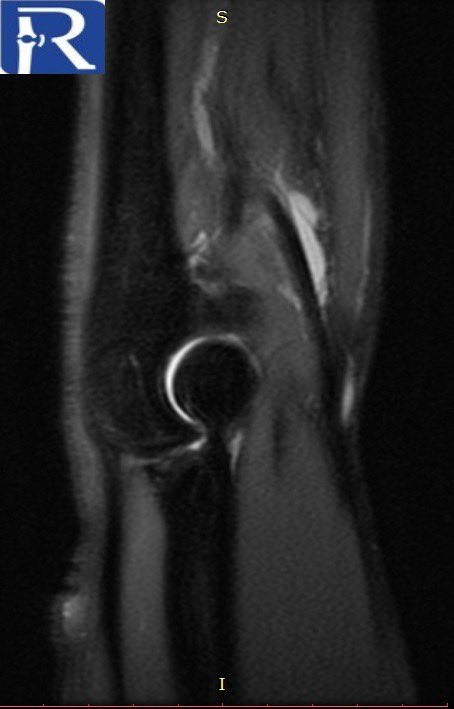

#CaseOfTheWeek‼️🥳‼️ ☢️🩻☠️Case#22☠️🩻☢️ #Mass 📲➡️➡️#Diagnosis❔❓❔ #FOAMRad #RadEd #MedEd #OrthoEd #OrthoTwitter @ssr_rwg @UWRadRes @ISSVA_org